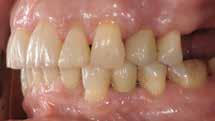

Den kliniske undersøgelse viser harmoniske ekstraorale sagittale forhold med skeletalt dybt bid (Fig. 1A, D). Hendes smil er alderssvarende med en eksponering på 8/10 af overkæbeincisiverne, mens smilets bredde er smalt med synlige mørke laterale rum (Fig. 1D). Underkæbeincisiverne er synlige under tale. Der ses neutrale okklusale forhold ved hjørnetænderne og neutrale pladsforhold i overkæben, men udtalt trangstilling i underkæben især lokaliseret i regio 1-1 (Fig. 1C).

Sliddet klassificeres som grad 2 (moderat tandslid) på de centrale incisiver i overkæbe og underkæbe. Det kan anses som patologisk, da det er atypisk for patientens alder, giver anledning til smerte/ubehag, og giver patienten et æstetisk problem. Der ses infraktioner af overkæbeincisiverne. Der ses endvidere en udtalt Spee-kurve i underkæben og ingen interincisal afstøtning på 2-2 med let ganepåbidning.

Røntgenanalyse viser fravær af -6 samt et velholdt tandsæt uden tegn på sygdom. Profilrøntgenbilledet viser et skeletalt

dybt bid, men normal inklination af fortænder i over- og underkæbe (Fig. 1B).